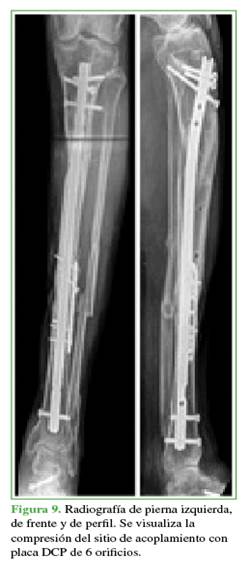

Una vez completado el transporte óseo, los pacientes pasan a la etapa de compresión del sitio de acoplamiento (Figuras 7 y 8). Esto se llevó a cabo mediante el sistema de transporte o la compresión con una placa de compresión dinámica sin invadir el foco (Figura 9).